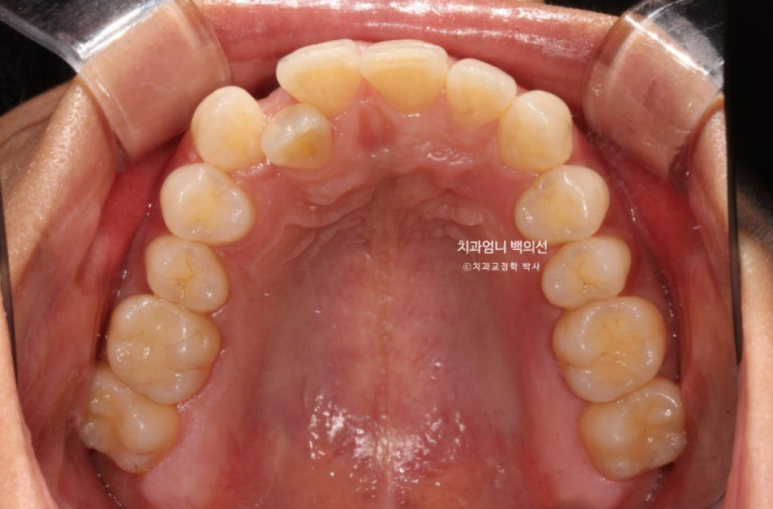

교합면에서 보면 입천장에 위치했던 덧니 뿌리 부분은 아직 입천장 쪽에 위치해 있습니다.

가지런해진 배열과 유지장치 모습입니다.

위 아래 앞니 중심선은 정확히 매치가 됩니다.

덧니는 잘 배열되었습니다.

치근흡수는 없고 치근평행도는 좋습니다.

인비절라인 교정은 철사 브라켓 교정에 비해서 치아에 가해지는 힘이 약한 만큼 경험상 오래 걸리는 교정이여도 전반적으로 치근흡수는 거의 없습니다.